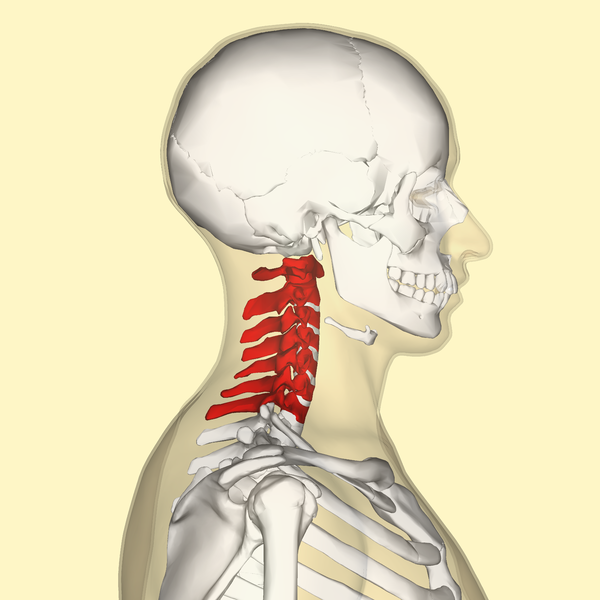

Whether it's from a fall or injury, back pain can be crippling. Getting to the doctor is the initial step in dealing with neck and back pain. You might be recommended medications, physical treatment, or other treatments to help alleviate pain. The pain may be local or spread across your entire back, or it might be connected with an underlying medical problem.

Pain in the back is a common condition, as well as lots of people experience it at some time in their lives. Usually, back pain is connected with muscle strains or soft tissue troubles. The pain might be a plain pains or an acute pain. It may be felt in the back, neck, and reduced legs. If the discomfort is severe, it may be associated with a herniated disc or another underlying clinical problem.

Your medical professional might likewise advise a series of imaging treatments to identify the cause of your pain in the back. These imaging treatments can consist of x-rays, bone scans, and CT scans. These imaging treatments can be handy, yet they aren't always necessary for the majority of situations of neck and back pain. If you have severe pain in the back, your physician might recommend an injection. These injections can help to ease pain as well as minimize inflammation.